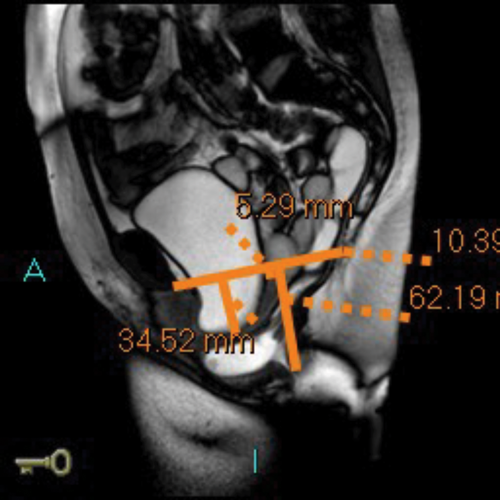

MR defecating proctograms are performed in a 1.5 Tesla MR scanner (Philips Sense). A similar detailed explanation of the procedure and consenting process takes place, so the patient knows what to expect during the three ‘cine’ scans of ‘squeeze up’, ‘bear down’ and ‘empty out’. The urinary bladder must be empty as far as possible during the MR scan.

After an initial digital rectal examination, 120mls of ultrasound jelly is instilled into the rectum via a rectal tube with the patient in the left lateral position. The patient is then turned to lie supine and positioned so that the top of the Sense-body coil is at same level with the iliac crest. The MRI scan protocol includes T2 axial and coronal sequences and sagittal ‘cines’ squeeze, bear down and two defecatory attempts with a couple of minutes rest in between. In cases of incomplete evacuation, a repeat evacuation may be needed or a coronal cine.

In addition the anterior and middle compartment is assessed, particularly for the presence and anatomy of a cystocoele or vault prolapse. The T2 sequences also allow pelvic evaluation for other incidental pathologies (Figure 2).

Figure 2a: Baseline MR proctogram.

Figure 2b: Pelvic floor descent MR proctogram.

Figure 2c: Large cystocoele MR proctogram.

Figure 2d: Large rectocoele on MR proctogram.